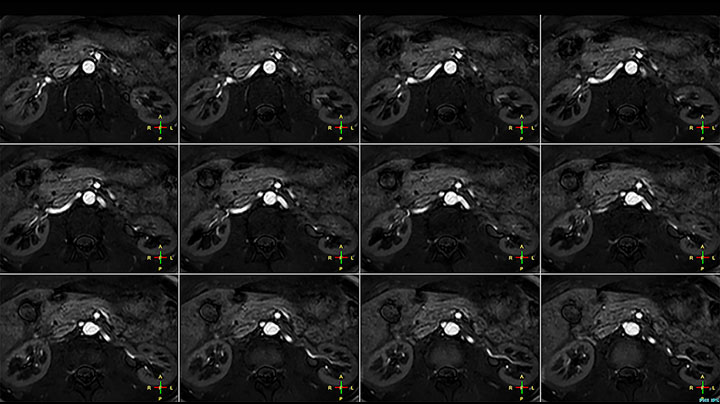

Positioning and operation: smooth and simple Once the scanner was in place, Mrs. Schiffer and her staff received tailored training in line with their clinical and workflow requirements and objectives. “I have been impressed from the start. Installation and set-up were smooth and simple. Within three days, our technologists were confidently using the new system,” recalls Mrs. Schiffer. Since installing Prodiva 1.5T, she and her team have noticed a number of enhancements to their daily work. The scanner’s simple Breeze workflow supports easy patient positioning with fewer positioning steps, rapid set-up and changeover times. Ultra-light anterior coils, short cables and small connectors are making technologists’ lives easier. Senior MRI technologist Sandra Maass says: “Speaking for myself and my colleagues, we all very much enjoy using Prodiva – and we benefit from its many workflow advantages every day.” And Mrs. Schiffer adds, “The flexible, lightweight coils fit really well to the patient’s body shape, and the connectors are superb: connecting and disconnecting requires just little effort.” “The shoulder coil is a great example of easy positioning with Prodiva,” says Mrs. Maass “Other shoulder coils can be quite rigid, so that patients with pain, or bigger stronger shoulders, or a somewhat abnormal shoulder or spine anatomy cannot be positioned well in the coil, which often leads to loss of image quality. However, the Prodiva shoulder coil is very flexible and has large coverage, which makes good positioning easier and that contributes to the superb image quality and high SNR that we get in our shoulder exams.” High quality of images impresses From a clinical perspective, too, Mrs. Schiffer is very impressed with Prodiva 1.5T. In her practice around 50% of scans are neurological, 40% musculoskeletal and the rest made up of vascular, abdominal and miscellaneous cases. The radiology team is receiving good results across anatomies, which their referring physicians are confirming to them. “Prodiva’s high image quality and advanced features, including diffusion-weighted imaging in many organs, improve our diagnostic confidence and help decision-making,” says Mrs. Schiffer. “Prodiva has been an excellent investment and is definitely the right choice for us.” “The quality of the contrast-free MR angiography keeps impressing us,” says Mrs. Schiffer. “In addition to not having to inject contrast agent, these images are amazing, for instance of the carotids. Also our exams of shoulders and hands are really exceptional. Images of the hands, for example, cover the fingertips and include the full wrist as well, all with high signal-to-noise ratio.”

Prodiva imaging of the hand covers the fingertips and includes the full wrist as well. The dS MSK M coil is easy to use.

Scan time 2:55 min, FOV 160 mm, acq voxels 0.55 x 0.83 x 3.0 mm.